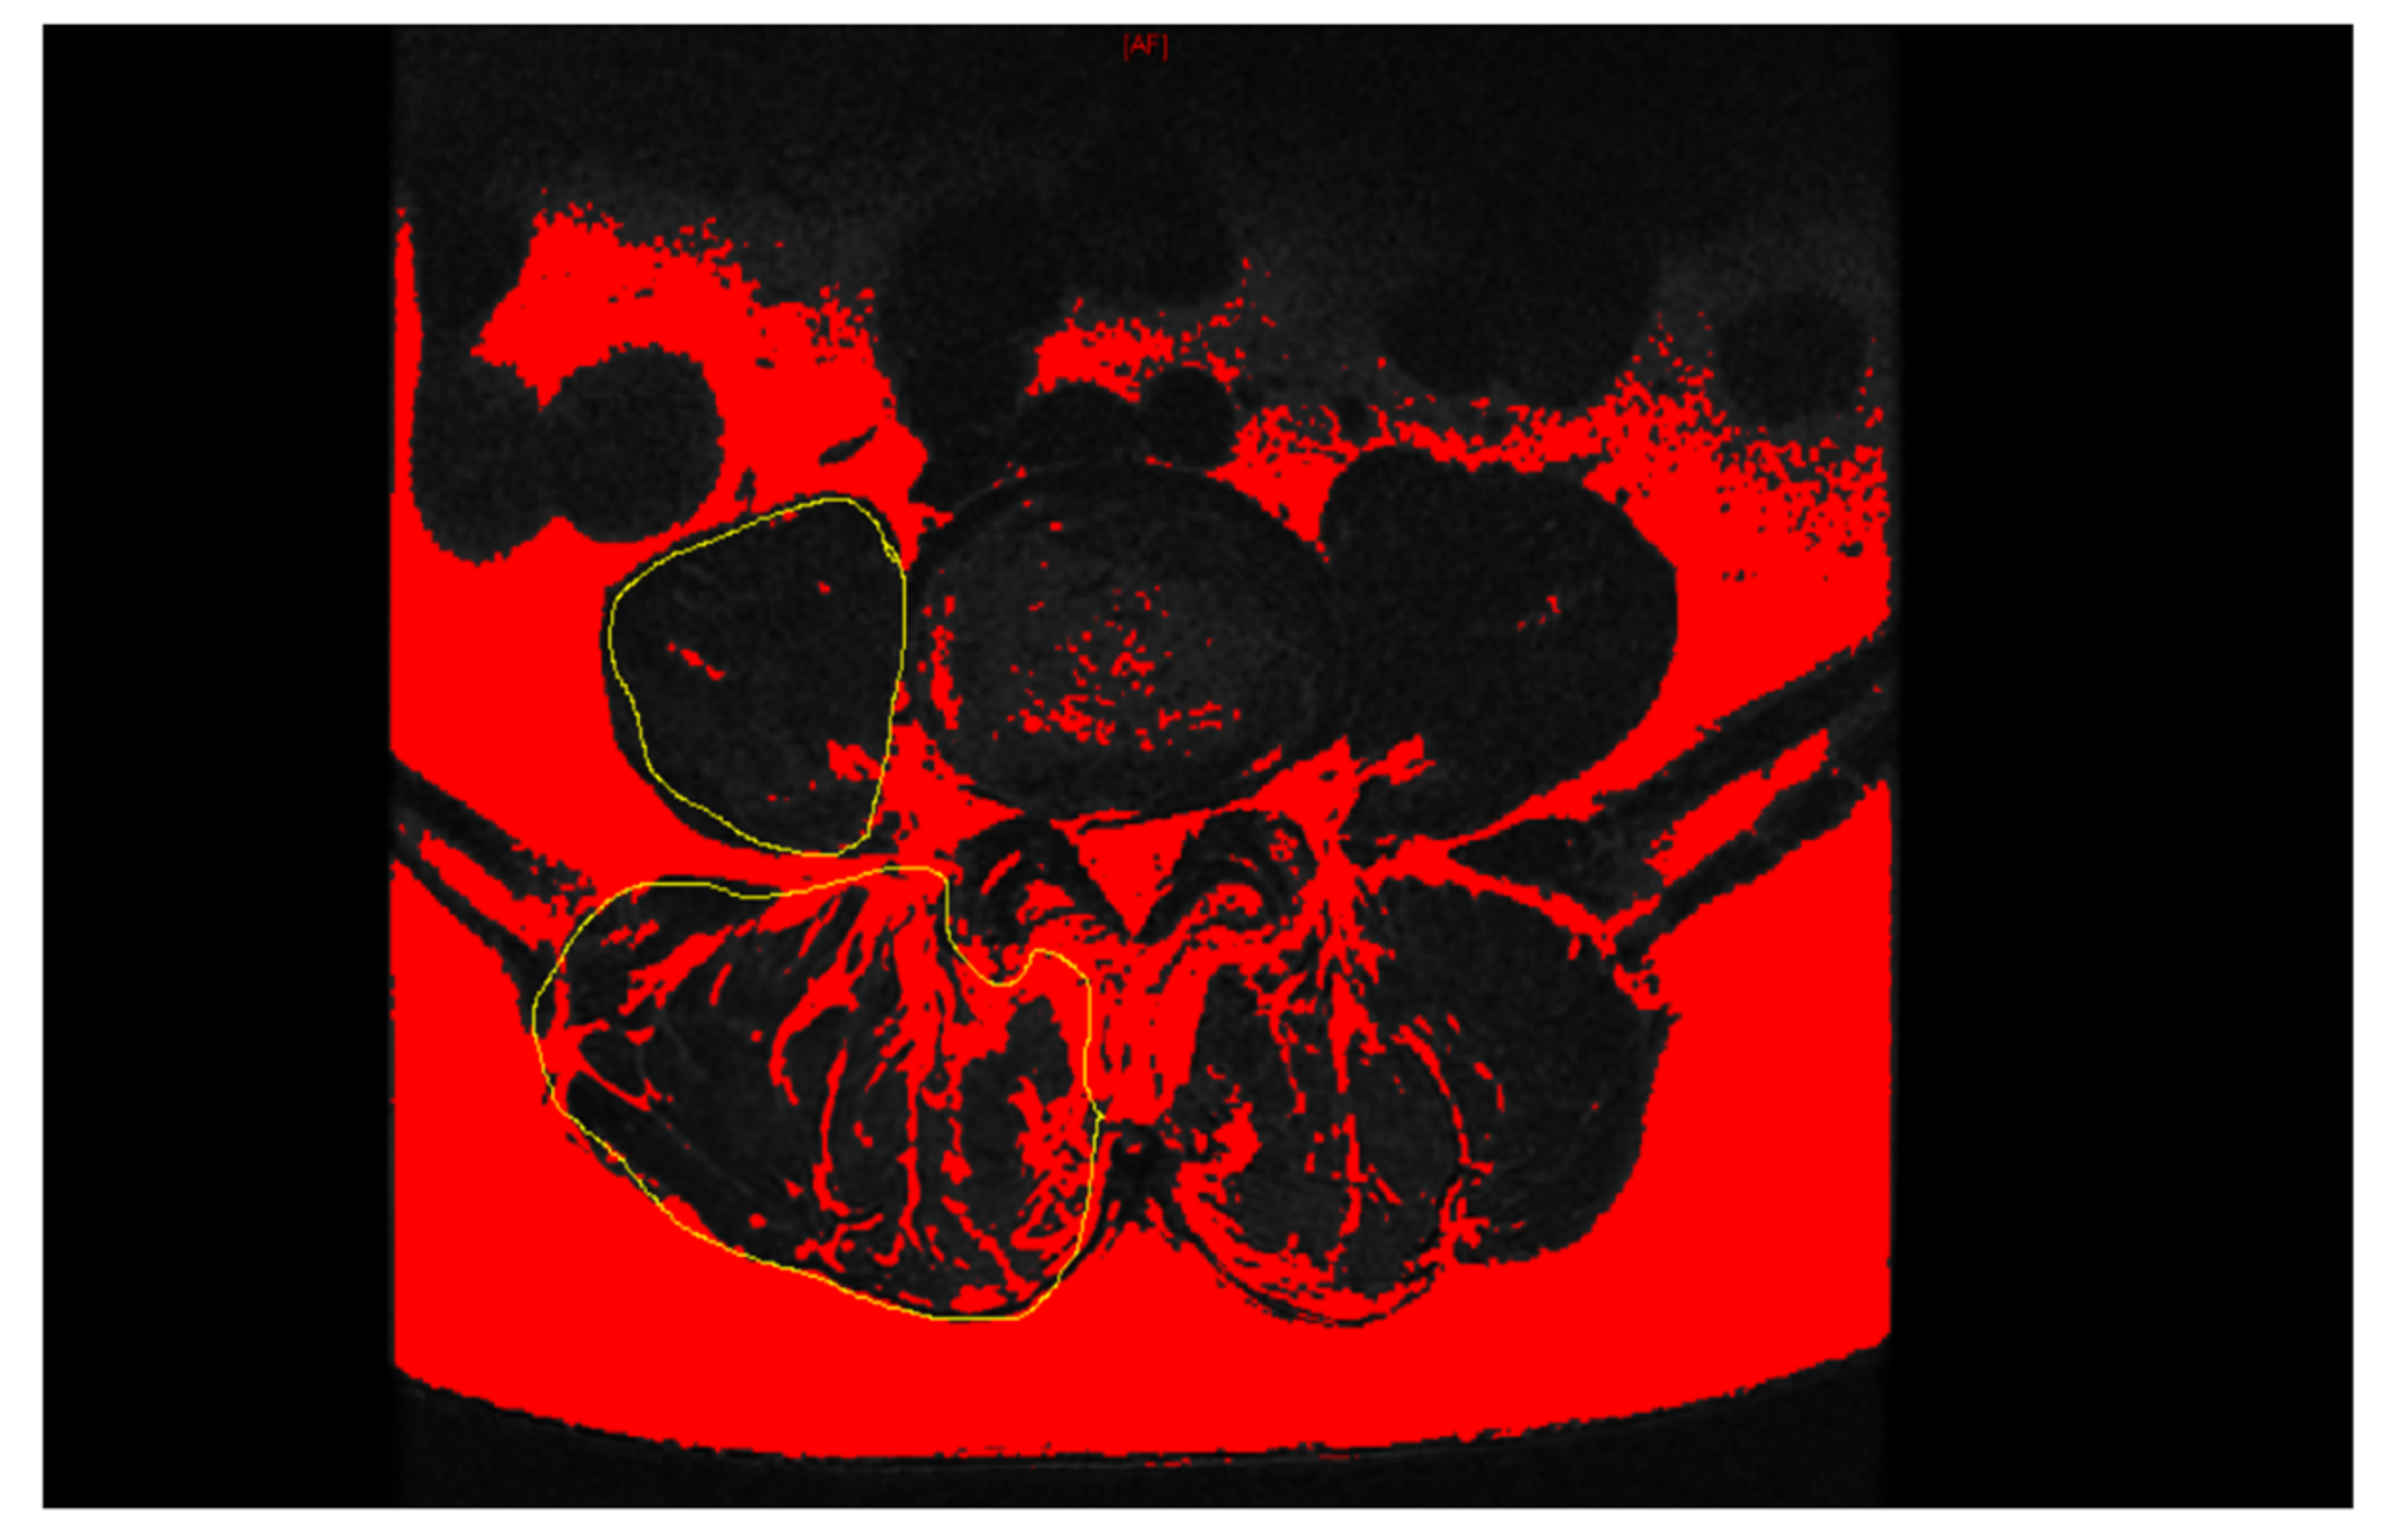

- Jeon, I.; Kim, S.W.; Yu, D. Paraspinal muscle fatty degeneration as a predictor of progressive vertebral collapse in osteoporotic vertebral compression fractures. Spine J. 2022, 22, 313–320. [Google Scholar] [CrossRef]

| PSM rCSA | 0.818 | 0.715–0.934 | <0.001 |

| PSM fatty degeneration | 0.783 | 0.756–0.807 | <0.001 |